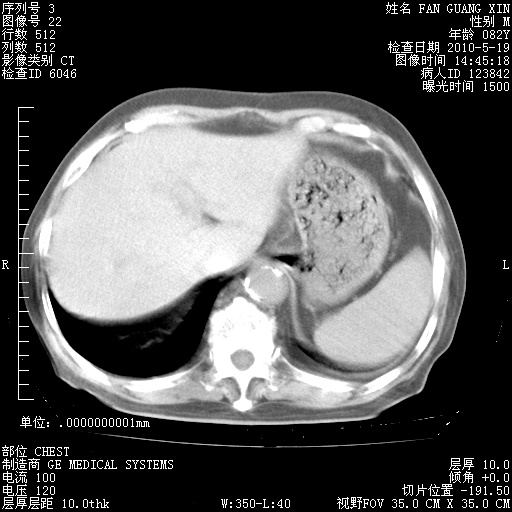

再治疗10天后的肺部CT 纵膈窗

阅读此次胸部CT,肺间质渗出性改变较入院时有吸收。目前从体温、白细胞、中性分叶明显增高,肯定存在细菌感染(发生医院感染哦,若无消化道及泌尿系统等感染的依据,肺部感染可能大)。若你院头孢哌酮舒巴坦钠耐药率较高,同意你的方案,若48小时体温仍高,可考虑使用碳青霉稀类抗菌药物,同时可予超声雾化、注意滴数时加大液体量。白蛋白33.30g/L较低哦,需加强营养等支持治疗。